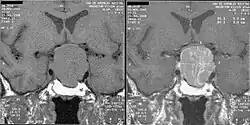

An MRI of the brain focusing on the sella turcica after gadolinium administration allows for clear delineation of the pituitary and the hypothalamus and the location of the tumor.